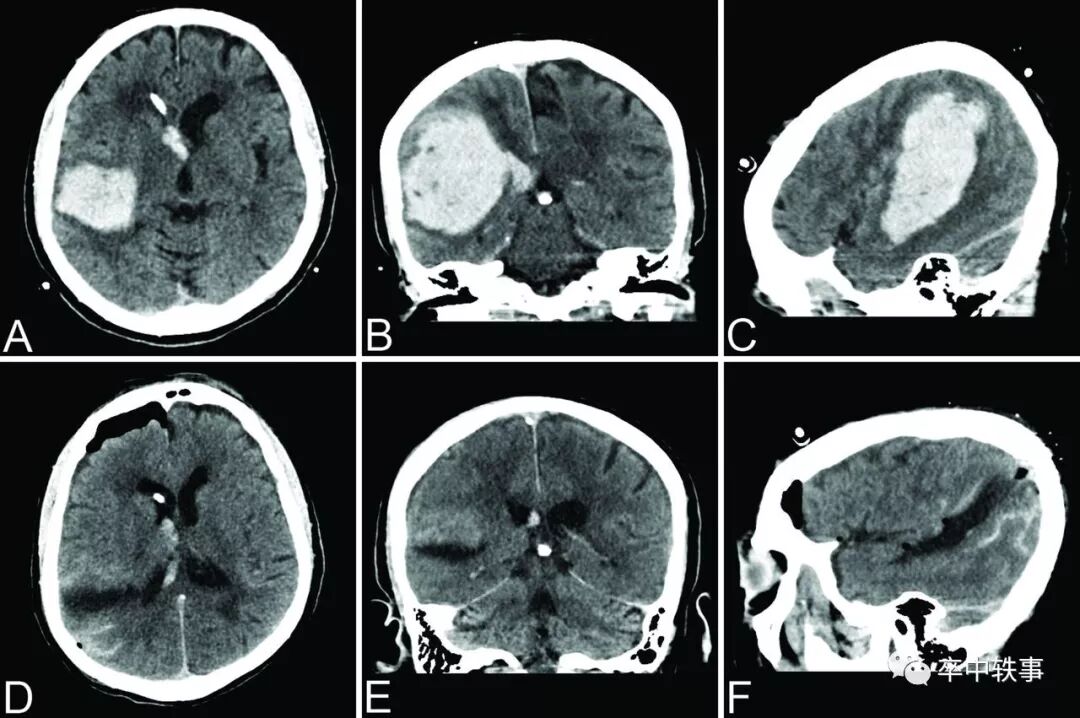

脑出血(上图)一般指脑小血管破裂,血液进入脑实质,形成 “外军入侵” 的占位性效应。严重时脑组织受压,脑室闭塞,中线结构移位。脑出血造成原发性脑损伤,占位效应加上血液 “毒性”,导致继发性脑损伤。

1982年西班牙 Valencia 的三位神外医生使用 Backlund 和 Holst 设计的仪器,在 Applied Neurophysiology 报道了16例病人脑血肿的清除结果(上图)。

其中一例失败,二例效果不好,十三例几乎彻底清除了血肿,解除了占位效应。

但是病人死亡率高达81%(二例术后好转后因肺炎而死,二例术后好转后因再出血死亡),死亡率与入院时意识障碍有关,与开颅手术清除脑血肿死亡率83%类似。

1990年第四军医大学神经内科和急诊科的郝登荣和粟秀初在《中国神经精神疾病杂志》报道了3例经皮枕骨钻孔穿刺抽吸治疗自发性小脑出血性血肿(上图),都是急性期手术。

第一个病人第六天用脑血管造影穿刺针抽出血块12毫升,打入尿激酶6000单位,6小时后又抽出40毫升血块。术后头痛减轻,3个月后恢复。第二例四天时抽出8毫升血块,打入尿激酶6000单位,6小时后又抽出12毫升血块,三个月后恢复。第三例四天时抽出19毫升,两次尿激酶后又抽出14毫升。术后八天因肺炎死亡。

作者认为微创手术加尿激酶简单安全,推荐使用。

同年齐齐哈尔医学院附属二院神经科徐景林,王文举,周杰信和赵俭在院学报上发表了用14号脑穿针钻颅血肿抽吸疗法与药物疗法各30例比较(上图)。

都是急性期手术,初次抽取后注入一万单位尿激酶,然后再抽取血肿。手术组好转率86%,药物组60%,死亡率手术组13%,药物组40%,皆有显著区别。

作者认为微创手术加尿激酶创伤小,简单,安全,有效,积极推荐。

脑出血外科治疗则进退两难。小血肿病人不需要手术,大血肿昏迷病人手术效果不佳,所以脑血肿手术是针对GCS 6-12而且继续恶化的病人群(上图)。